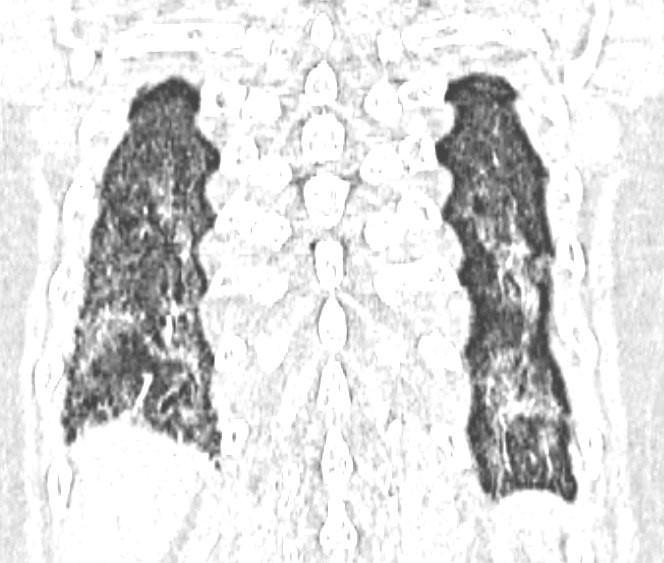

Kết quả xét nghiệm miễn dịch cho thấy sự hiện diện của nhiều tự kháng thể đặc hiệu. Chụp cắt lớp vi tính phổi phát hiện tổn thương phổi kẽ.

Hình ảnh hai phổi bị xơ hóa của bệnh nhân.

Từ các dữ kiện lâm sàng và cận lâm sàng, bệnh nhân được chẩn đoán mắc xơ cứng bì hệ thống thể giới hạn, kèm theo bệnh phổi kẽ và một số rối loạn liên quan đường tiêu hóa.